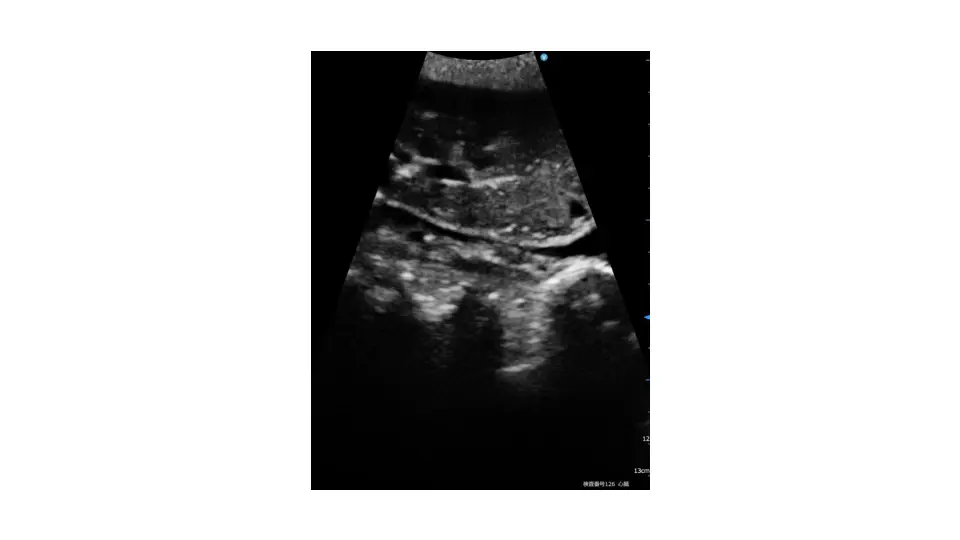

病の軌跡に寄り添う -C→D→終末期→看取りとその先に寄り添う心不全診療